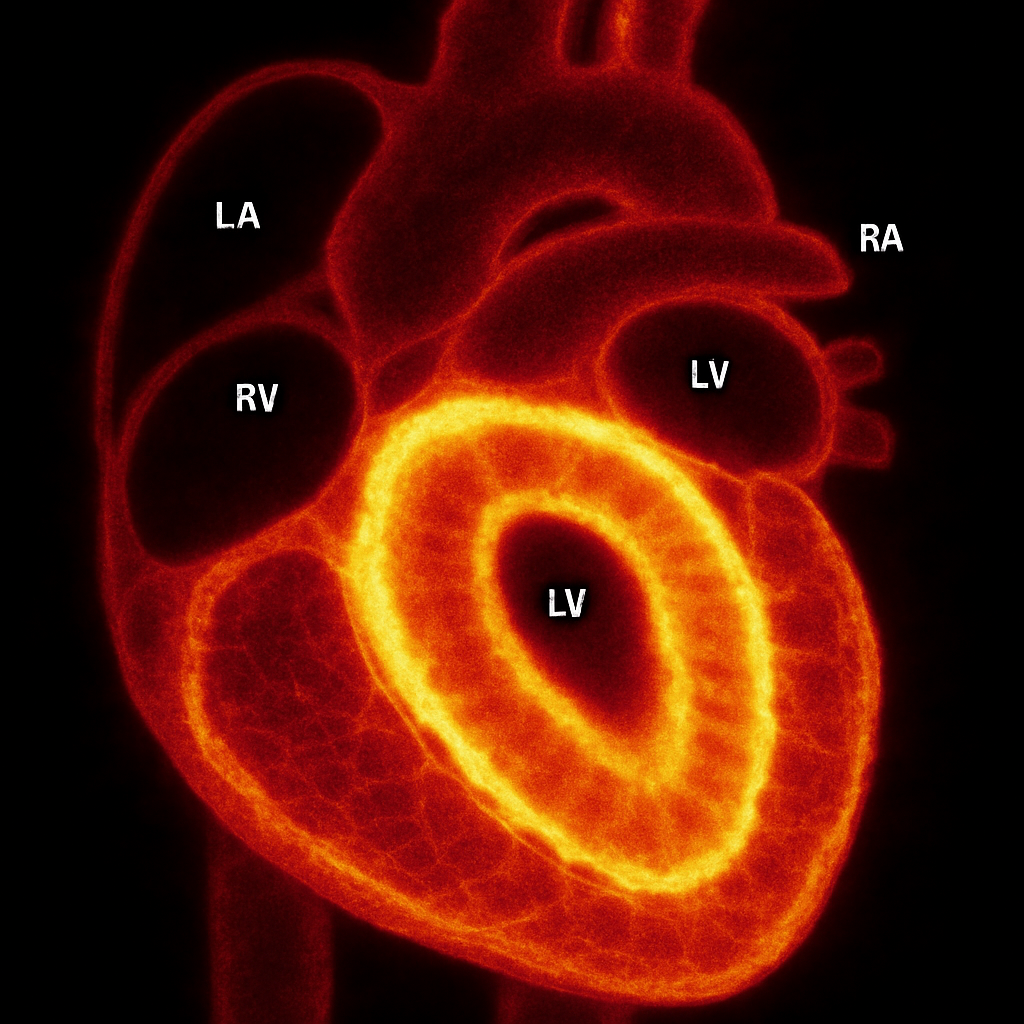

MRI — Short Axis Cine (Diastole)

Cardiac MRI short-axis (SA) view at mid-ventricular level during end-diastole. Balanced SSFP sequence showing bright blood in LV and RV cavities, dark myocardium, papillary muscles.

Ssfp Short Axis

bSSFP cine, mid-ventricular short axis, end-diastolic frame. Bright blood pool, dark myocardium.